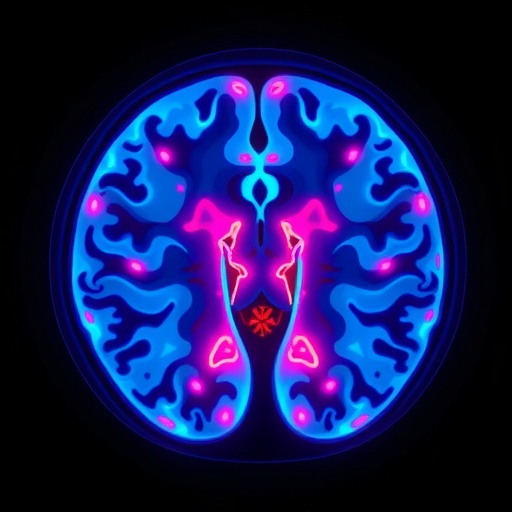

The new research leverages cutting-edge high-resolution structural magnetic resonance imaging (MRI) at 3-Tesla strength to probe the habenula’s intricacies in patients experiencing their first episode of depression, who have not yet undergone any antidepressant treatment. This focus on first-episode depression (FED) patients eliminates confounding effects of long-term medication or illness chronicity, allowing for a purer insight into the neurobiological underpinnings of early depressive pathology.

Traditional MRI assessments often rely on gross volumetric analysis or signal intensity parameters, but such approaches may overlook subtle, spatially heterogeneous changes within the habenular complex. To circumvent this limitation, the study incorporated advanced voxel-based radiomic analysis coupled with clustering algorithms. Radiomics extracts a high-dimensional array of quantitative imaging features that capture voxel-level variations in texture, intensity, and spatial distribution, potentially revealing microstructural and molecular alterations invisible to conventional imaging metrics.

The investigation enrolled 94 participants split evenly between healthy controls and patients with first-episode depression. Precise segmentation of the habenula was performed, followed by detailed measurements of volumetric size and T1 relaxation times—a parameter sensitive to tissue composition and microenvironment. These neuroimaging markers were analyzed in relation to age, depression severity, and other clinical parameters, providing an integrative picture of habenular changes associated with early depressive states.